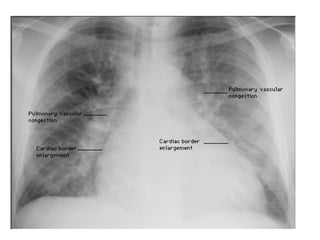

Chest x ray

• 14.

Check the Heart •Size • Shape • Silhouette-margins should be sharp • Diameter (>1/2 thoracic diameter is enlarged heart) Remember: AP views make heart appear larger than it actually is.

Check the costophrenicangles Margins should be sharp

• 19.

Loss of SharpCostophrenic Angles